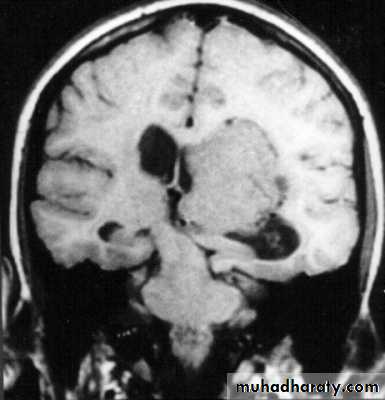

Copper-beating’ marking

Skull X-ray findings in increased intracranial pressure

• Sutural separation in children.

• ‘Copper-beating’ marking of the cranial vault.

• Thinning of dorsum sellae.

• Erosion of the posterior clinoid process.